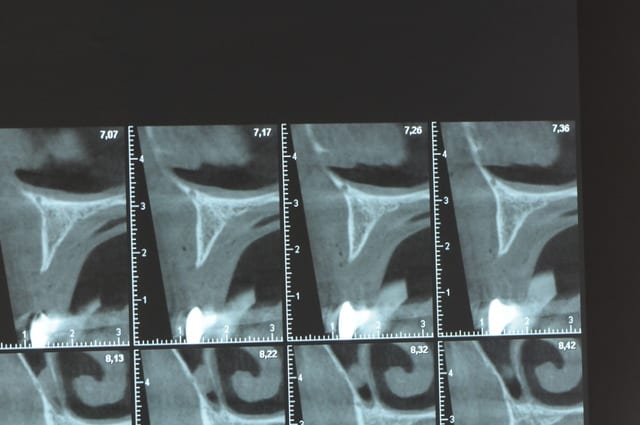

Une petite étude de ton cas D57

Les zones exploitables radiologiquement parlant:

Coupes implant

2,3 40100

4,96 35130 avec sinus lift mais difficile

5,25 35150

6,02 35130

6,78 35115 après réduction de hauteur de crête

7,26 35115 après réduction de hauteur de crête

8,51 35150

10,43 40115 ou 50115

11,10 40115

Ce qui nous fait 9 implants possible évidement avec un comblement de sinus on augmenterait encore les zones implantable mais ce n’est pas le but recherché, avec 8 (4+4) il doit être possible de faire une belle barre support de complet